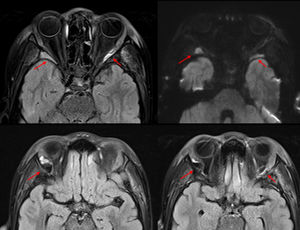

We present the case of an eight-year-old patient with sickle cell disease homozygous for HbS (with no family history) managed with prophylactic amoxicillin, hydroxyurea and folic acid, under annual follow-up, with a previous admission due to a vaso-occlusive crisis in the leg and no other relevant history. She was admitted to the sending hospital with suspected vaso-occlusive crisis in the extremities and abdominal pain and transferred to our hospital due to progressive deterioration with fever, hepatomegaly and splenomegaly extending to the iliac crest, in addition to painful bilateral periocular edema in absence of phlogosis or changes in vision (Fig. 1). The bloodwork revealed a decreased hemoglobin concentration and platelet count and elevated hemolysis markers, with a proportion of sickle hemoglobin (HbS) of 44.3% and a C-reactive protein level of 17.7 mg/dL. Splenic sequestration and orbital cellulitis were suspected,1,2 leading to administration of supplemental oxygen, analgesia with continuous infusion of morphine, two red blood cell transfusions and intravenous antibiotherapy. The orbital CT scan (Fig. 2) showed bilateral involvement of soft tissues in the outer periorbital region, bordering the orbital rim and extending posteriorly, a finding that could be compatible with extramedullary hematopoiesis or a lymphoproliferative disorder. The head MRI (Fig. 3) ruled out nervous system involvement and showed areas suggestive of infarction in the great wings of the sphenoidal bones with secondary hemorrhagic effusion.3 The blood culture and the antibody test for Epstein-Barr virus were negative. A diagnosis of bone infarction was made and antibiotherapy discontinued, with full clinical resolution in seven days.